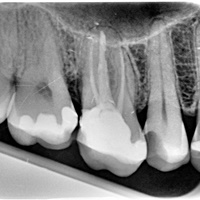

Pacjent z bólem, nieudana próba udrożnienia kanałów pod mikroskopem. Decyzja o resekcji korzenia policzkowego dalszego. RTG kontrolne rok po zabiegu.